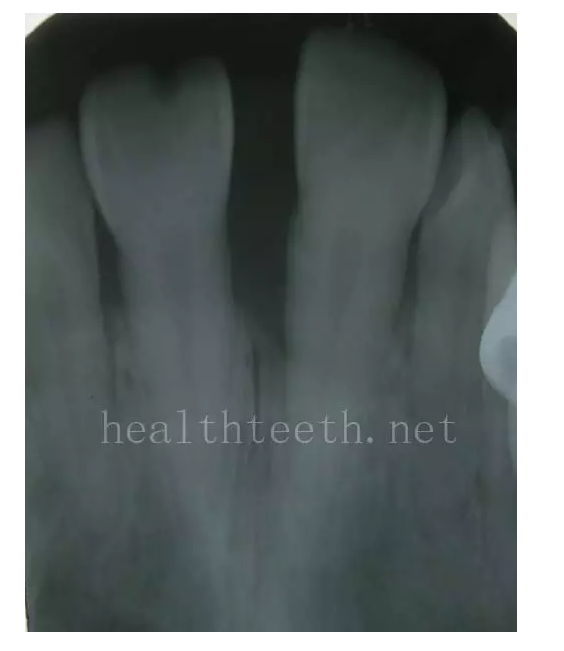

牙片顯示牙槽骨的垂直吸收

前門牙因為牙周炎骨質(zhì)破壞造成牙齒的松動、移位